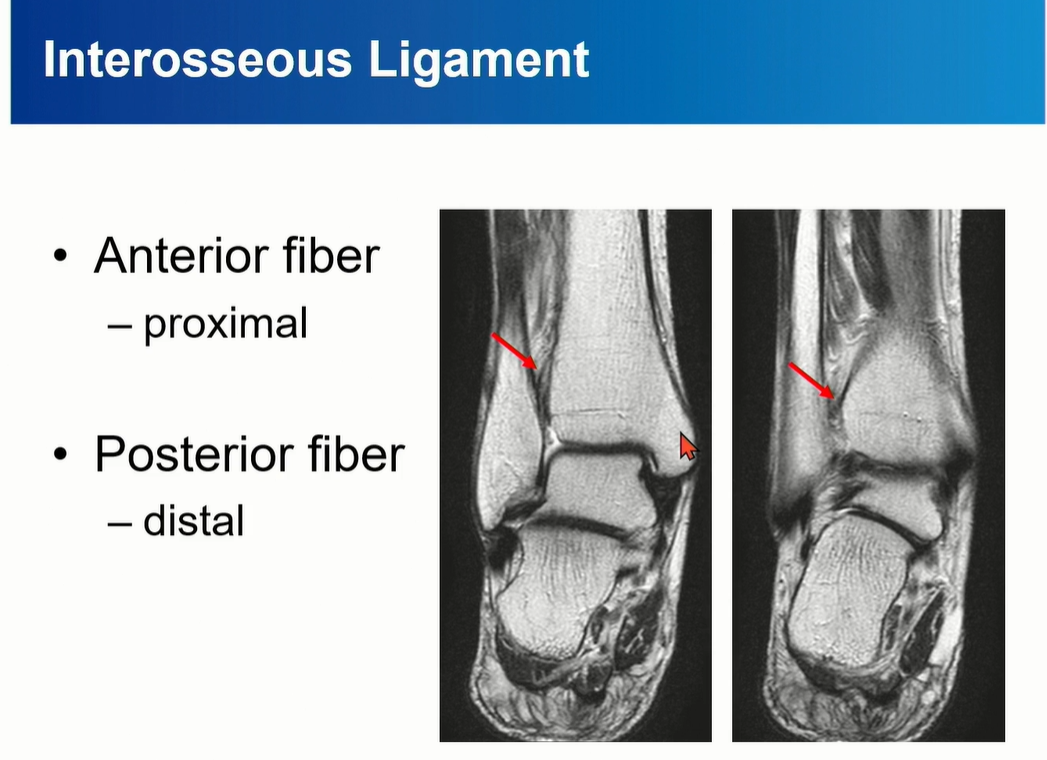

4-1. Interosseous Ligament

Anterior fiber가 proximal에 위치, posterior fiber가 distal에 위치하게 된다.

Tibia의 fibular notch와 fibula를 연결하는 역할을 한다.